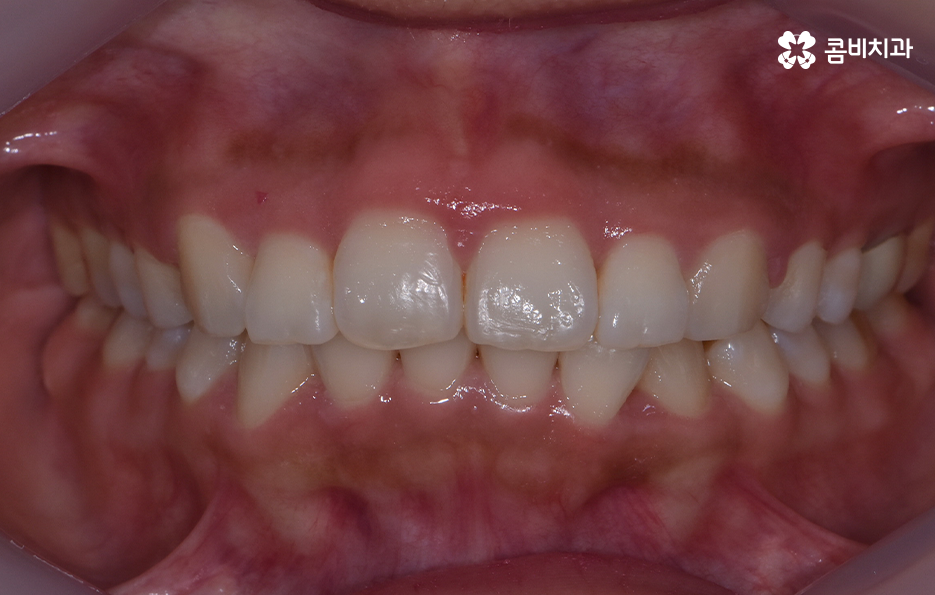

앞니가 살짝 틀어져 있다는 사실은 이미 전부터 알고 있었어요 하지만 그때는 이 정도면 괜찮겠지, 사람마다 치열이 완벽하게 곧을 필요는 없겠지 하며 대수롭지 않게 넘겼어요 거울을 볼 때 조금만 입술을 다물어도 크게 티가 나지 않는 것 같아 굳이 치료를 생각하지 않고 지냈어요

그런데 어느 순간부터 누군가와 마주보고 웃을 때, 사진을 찍을 때, 말을 할 때조차 그 작은 틀어짐이 내 시선의 중심에 자꾸 걸리기 시작했어요

내가 생각하는 나의 이미지와 거울 속 모습 사이의 미묘한 차이가 점점 더 크게 느껴졌어요 처음엔 가벼운 걸림이었지만 시간이 갈수록 그것이 확실한 고민으로 바뀌어 갔어요 특히 사진을 찍을 때마다 그 불편함이 더 선명하게 다가왔어요

친구들과 함께 찍은 평범한 사진에서도 내 앞니가 살짝 돌아가 있는 모습이 먼저 눈에 들어왔어요 남들이 보기엔 별게 아닐 수도 있지만 정작 본인에게는 그 작은 비대칭이 너무 크게 느껴지는 순간들이 있었어요 이 불편함이 점점 일상 속 행동까지 바꾸기 시작하면서 드디어 교정을 고민하게 되었어요

특히 앞니는 사람의 첫인상과 발음을 결정짓는 중요한 치아라 조금만 틀어져도 눈에 잘 띄고, 스스로도 불편함을 크게 느끼게 되는데 앞니 틀어짐 교정 방법의 차이는 기본적으로는 치열의 복잡성이나 치아가 이동해야 하는 정도, 교합 등의 차이에서 나타나기 때문에 치료 방법을 구체적으로 이해하기 위해서는 앞니가 틀어지는 원인과 치아교정의 원리를 알아가는 것이 도움이 될 거예요

앞니 틀어짐 교정 방법 경미한 수준일 때는 부분 교정 방식은 치료 기간이나 방법 면에서 비교적 간단한 치료가 가능한데 앞니 6개 정도에만 브라켓을 부착해 미세한 틀어짐을 바로잡는 방식으로 치아가 크게 회전하지 않았거나 공간이 약간 부족한 정도라면 효과적이며 기간도 보통 3~6개월로 짧은 편으로 이 방식은 앞니 배열을 빠르게 정리하면서도 자연스러운 라인을 만들 수 있어요.